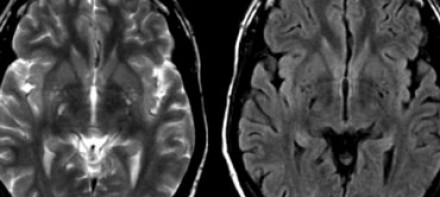

血管周圍間隙

圖片三:T2加權(quán)成像和FLAIR成像

請查看上圖并描述其病變特點。我們可以看到,在T2加權(quán)成像上,在基底節(jié)上有多個高密度病灶。在FLAIR成像上,這些病灶呈黑暗模糊影,在所有序列成像上,與腦脊液的密度相近(在T1加權(quán)成像上呈低信號)。

結(jié)合信號密度和病灶部位,可以判斷是典型的血管周圍間隙。

圖片四:FLAIR成像

血管周圍間隙是穿透軟腦膜血管周圍的腦脊液間隙。通常位于基底神經(jīng)節(jié)、腦室周圍、前連合附近以及腦干中間。在MR成像圖像上,在所有序列上的密度與腦脊液的密度相近。與其他白質(zhì)損傷病灶不同,血管周圍間隙在FLAIR和PD成像上呈黑暗模糊影,通常比較小,位于前連合附近的除外,此處的血管周圍間隙比較大。

在上圖中,我們可以看到比較寬的血管周圍間隙和在白質(zhì)中有融合的高密度信號病灶。該圖像很好的顯示了血管周圍間隙和白質(zhì)損傷病灶之間的差異。

由于周圍結(jié)構(gòu)組織的萎縮,血管周圍間隙會隨著衰老和高血壓而逐漸增寬。